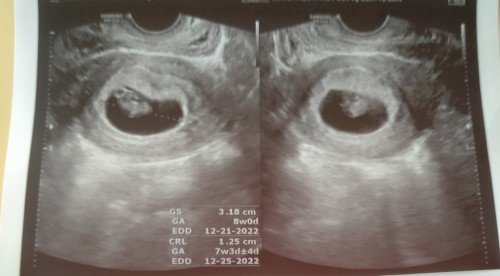

Hello mga mii. Ask ko lang po if normal lang ba na hindi pa makita ang embryo @6 weeks? Nagpa tv kasi ako kanina after kong mag positive sa 4 pts. Sabi ng ob ko masyadong maliit pa daw too early pa. Pero meron nang parang maliit na circle sa uterus ko. Niresetahan nya lang ako ng duphaston 2x a day, pampakapit daw kay baby. Balik daw ako after two week para i-check kung meron na. May same case po ba sakin dito? Kinakabahan po kasi ako. Ps. First pic po ay yung pt ko this morning while 2nd pic ay pt ko after kong magpa ob this afternoon around 2pm. #firsttimemom #3yearsttc